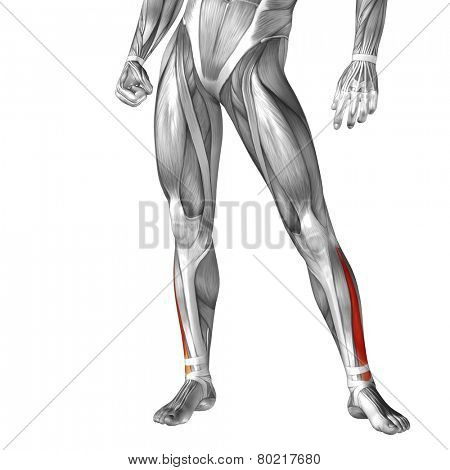

Extensor